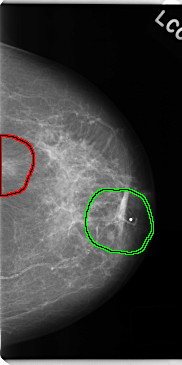

C_0146_1.LEFT_CC

FILE: C_0146_1.LEFT_CC.OVERLAY

TOTAL_ABNORMALITIES 2

ABNORMALITY 1

LESION_TYPE MASS SHAPE OVAL MARGINS ILL_DEFINED

ASSESSMENT 4

SUBTLETY 4

PATHOLOGY MALIGNANT

TOTAL_OUTLINES 1

BOUNDARY

ABNORMALITY 2

LESION_TYPE MASS SHAPE IRREGULAR MARGINS ILL_DEFINED

ASSESSMENT 5